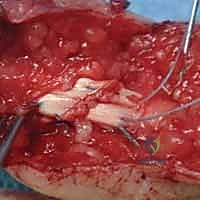

2. الشق الجراحي (Incision)

لا يتم قطع الجلد بشكل مستقيم أبداً لتجنب الانكماش الندبي. يستخدم الجراح شقوقاً متعرجة مثل شق برونر (Bruner Zig-Zag Incision) أو الشق الجانبي الأوسط (Mid-lateral). هذا يسمح بكشف واسع للأوتار مع حماية الأعصاب والأوعية الدموية.

3. استكشاف الأوتار وتحديد الأطراف (Retrieval)

هذه هي المرحلة الأكثر دقة. يجب العثور على طرفي الوتر المقطوع. في المنطقة الثانية، قد ينسحب الطرف القريب إلى راحة اليد. يستخدم الجراح أدوات مجهرية دقيقة وقثاطير مرنة لسحب الوتر بلطف دون إتلاف سطحه الأملس، وتمريره مرة أخرى عبر نظام البكرات (Pulleys).

4. تقنيات الخياطة الجراحية (Suturing Techniques)

الهدف هو تحقيق خياطة قوية بما يكفي لتحمل الحركة المبكرة، وفي نفس الوقت ملساء بما يكفي لتنزلق داخل الغمد الضيق.

* الخياطة الأساسية (Core Suture): يتم استخدام خيوط قوية غير قابلة للامتصاص. يعتمد د. هطيف على تقنيات حديثة متعددة الخيوط (4-strand أو 6-strand repair) مثل تقنية (Strickland) أو (Modified Kessler). كلما زاد عدد الخيوط العابرة للوتر، زادت القوة، ولكن زاد حجم العقدة، لذا فالتوازن مطلوب.

* الخياطة المحيطية (Epitendinous Suture): بعد الخياطة الأساسية، يتم استخدام خيط رفيع جداً (مثل 6-0) لخياطة الحواف الخارجية للوتر بغرز مستمرة. هذه الخطوة تزيد من قوة الإصلاح بنسبة تصل إلى 30% وتجعل سطح الوتر أملساً جداً لتقليل الاحتكاك والالتصاقات.

5. التعامل مع الغمد والبكرات (Pulley Management)

يحرص د. هطيف أشد الحرص على الحفاظ على بكرات A2 و A4. إذا تم قطعها أثناء الإصابة، يتم ترميمها لضمان عدم حدوث تقوس للوتر (Bowstringing) مستقبلاً.

6. إصلاح الأعصاب والأوعية الدموية

نظراً لأن الأعصاب الرقمية تسير بمحاذاة الأوتار، يتم فحصها بدقة تحت الميكروسكوب الجراحي. إذا كانت مقطوعة، يتم خياطتها باستخدام خيوط مجهرية دقيقة جداً (9-0 أو 10-0) لاستعادة الإحساس للإصبع.